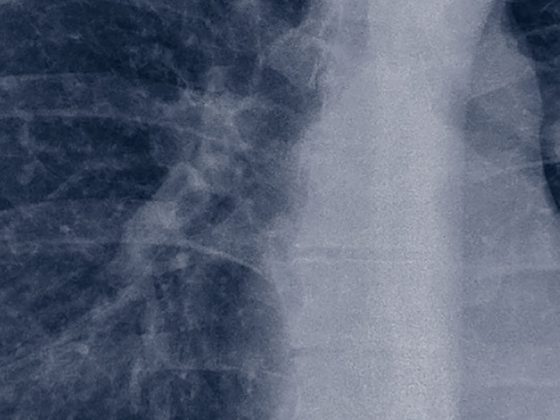

Pneumologie – Covid-19: ein Rückblick